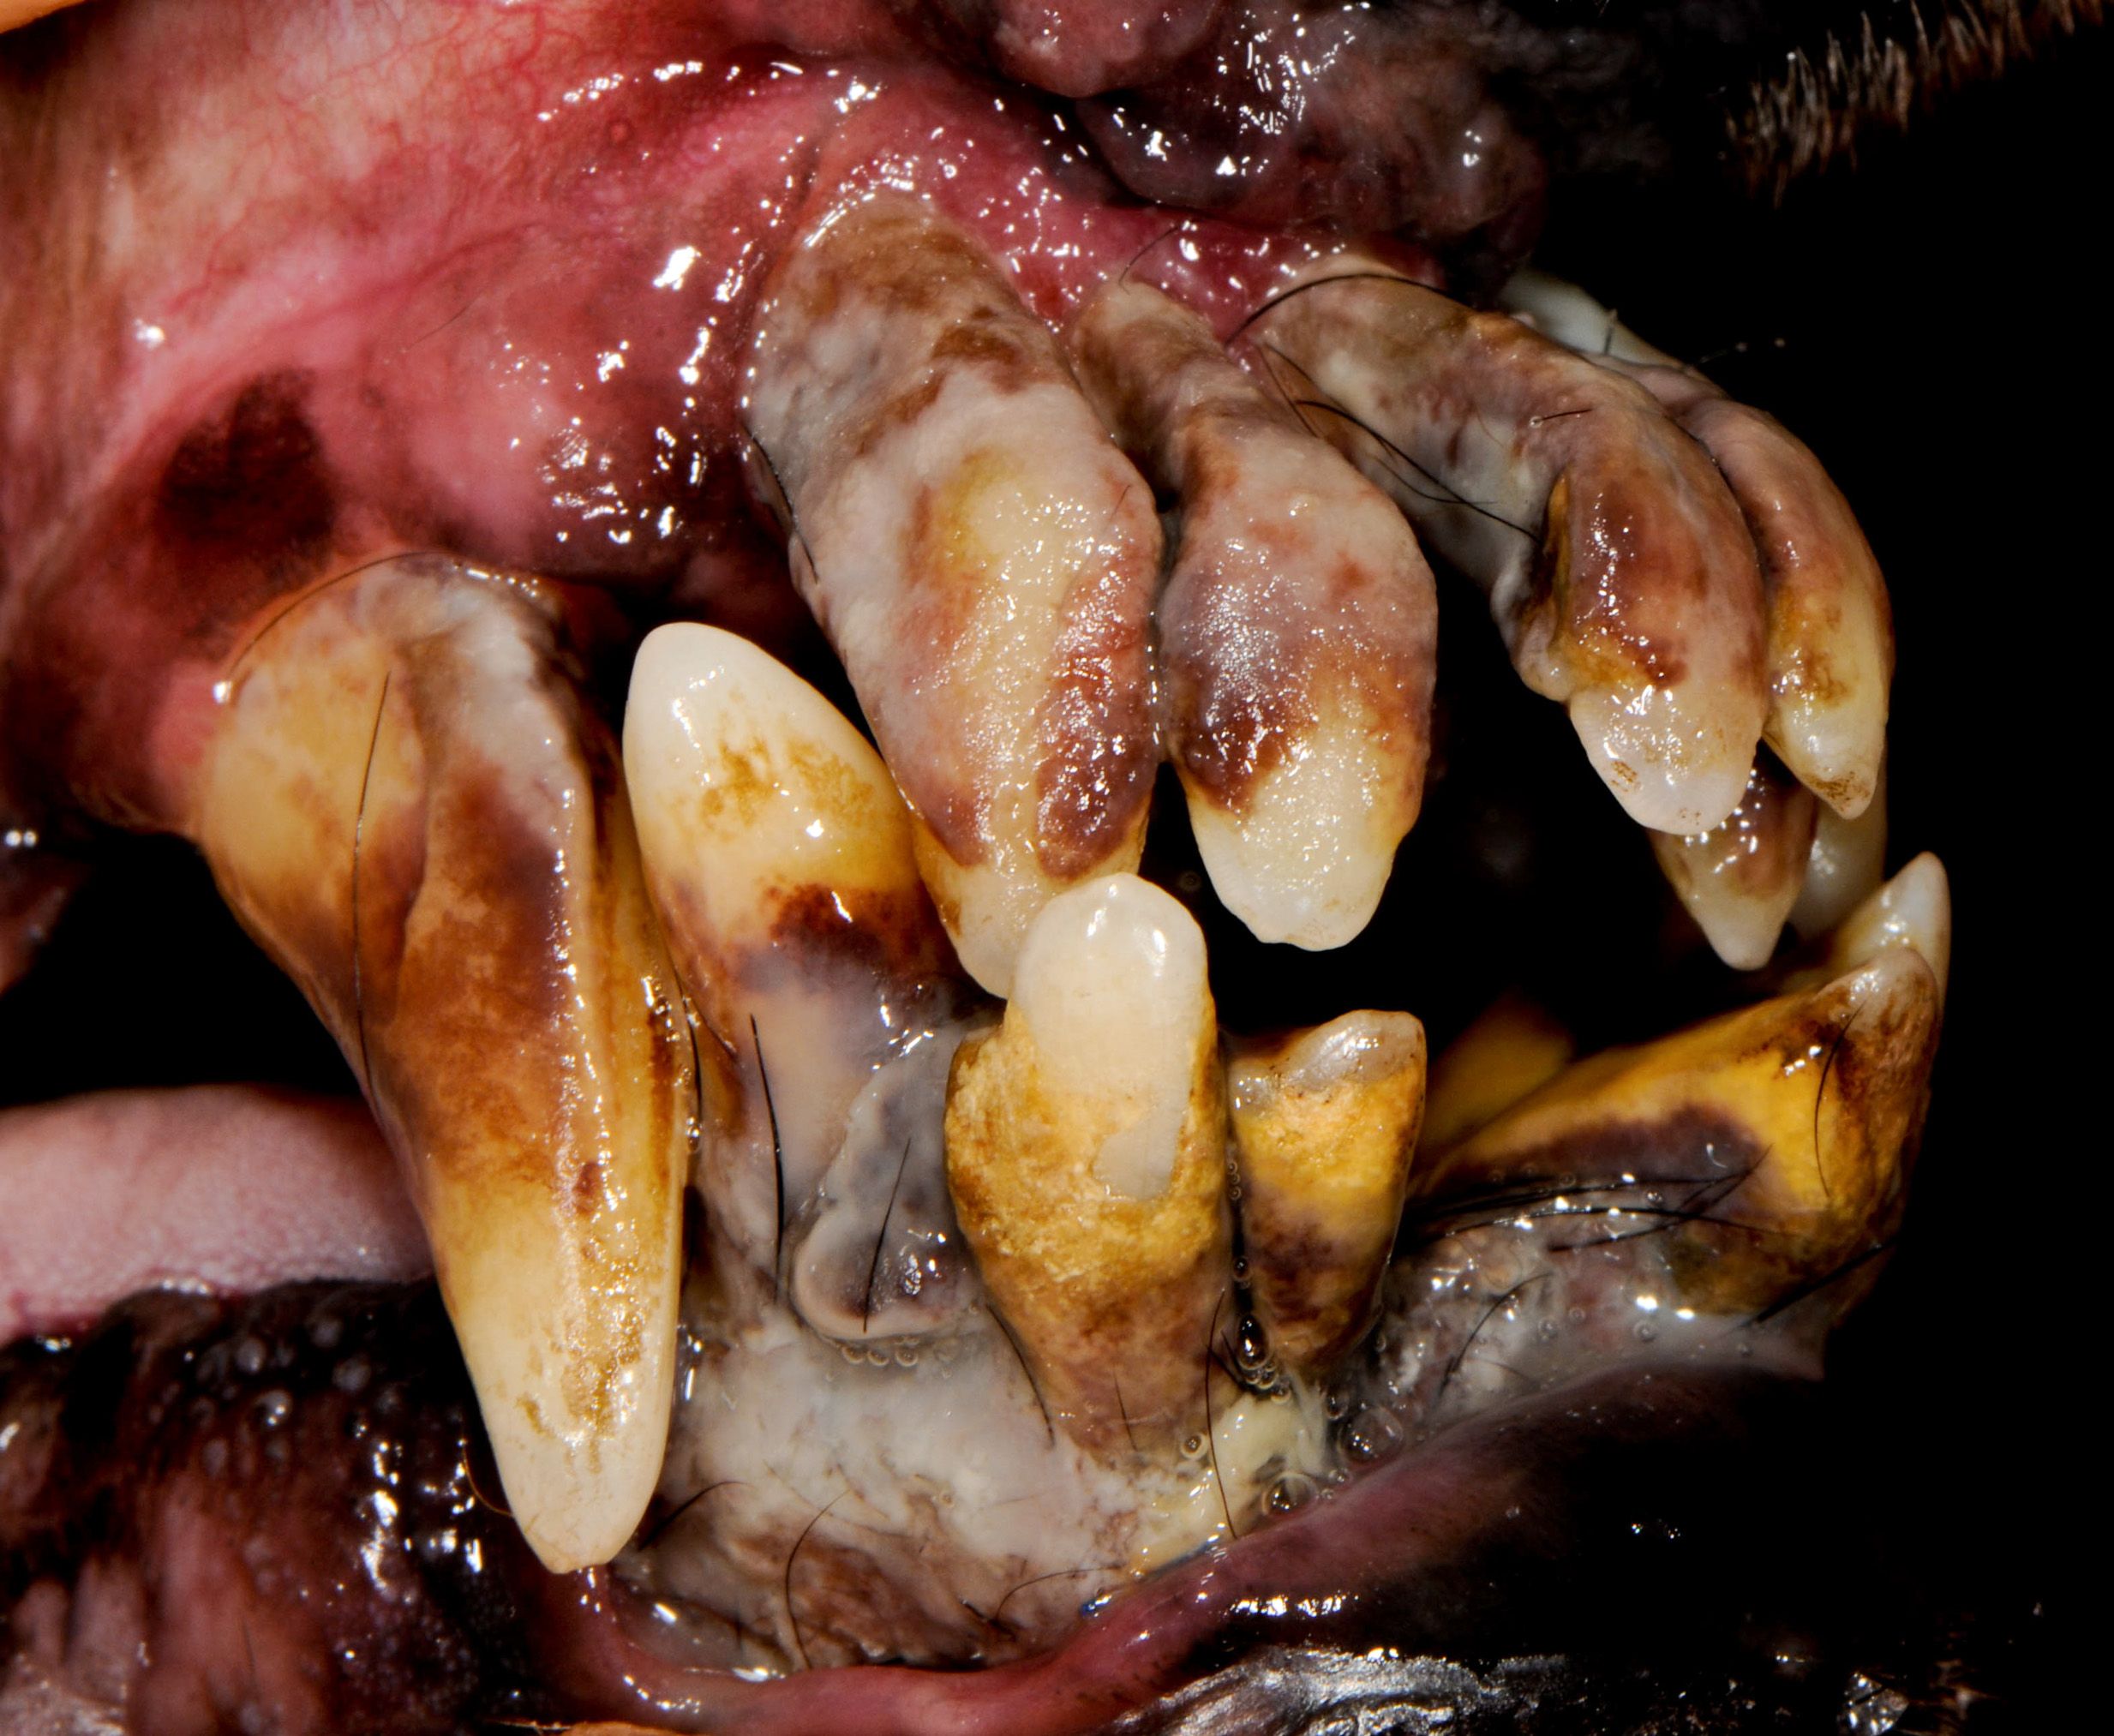

Advanced periodontal disease in dog.